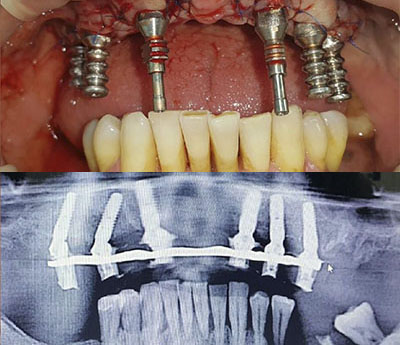

Sistemul Fast&Fixed este o alternativă imediată. Această procedură îți va permite să-ți recapeți zâmbetul și încrederea în sine într-un timp scurt. Deși rezultatul este imediat, durata de viață a acestui implant este pentru o perioadă îndelungată.

Este un sistem inovativ care permite o fixare rapidă și de lungă durată a dinților lipsă. În acest caz se folosește osul nativ al pacientului. În acest fel sunt eliminate alte intervenții adăugătoare, cum ar fi creșterea masei osoase. Acest sistem presupune doar câțiva pași: consultarea, elaborarea unui set de analize, amprentarea dentară, inserarea implanturilor provizorii, refacerea arcadelor dentare, iar la final fixarea danturii definitive. De la consultare până la obținerea unui zâmbet impecabil te despart doar 24 de ore.